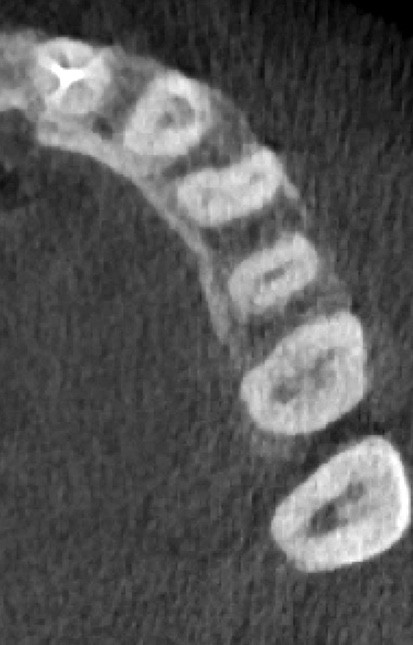

L’utilisation du scanner, et maintenant du CBCT, bouleverse l’idée très radiographique que nous avions du système canalaire.

En effet, la culture endodontique, fondée sur les critères radiographiques, a fait oublier les études de Hess et Zurcher (1925) qui mettent en évidence la complexité du système endo-canalaire [1]. Ce système présente une cavité principale (par exemple, le canal principal) ainsi que des canaux accessoires/latéraux. 25 % de ces microcanaux peuvent être interconnectés les uns aux autres, avec une densité plus importante de ramifications dans la région apicale du canal principal [2].

Rebondissant sur l’imagerie 3D et la mise en évidence des anatomies canalaires complexes, Peters, en 2001, décrit l’insuffisance instrumentale dans le traitement endodontique, et montre que 35 % des surfaces sont intactes après préparation canalaire correctement menée [18].

Endal, en 2011, montrait également, en utilisant le micro CT Scanner, l’insuffisance de nettoyage des isthmes inter-canalaires à nos techniques conventionnelles [19]. L’utilisation du laser Er:YAG devenait alors incontournable dans le nettoyage de ces isthmes et des zones non instrumentées (fig. 2 et 3).